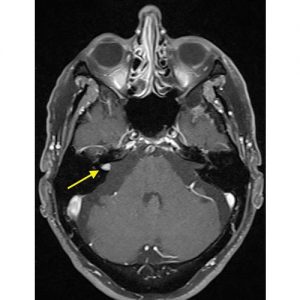

بسته به علائم، گاهی انجام MRI برای بررسی ساختارهای عصب شناختی درگیر در دستگاه شنوایی، توصیه می شود تا احتمال تومورها و اختلالات ساختاری عصبی بررسی گردد.

MRI